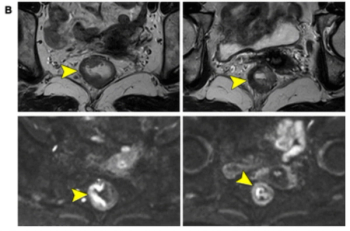

For women with breast-enhanced masses, Kaiser scoring (KS) demonstrated a 20 percent higher AUC than BI-RADS classification for contrast-enhanced mammography (CEM) and was comparable to KS for breast MRI.